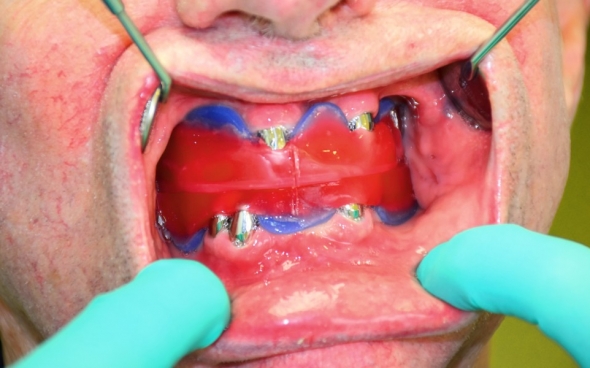

Metallkeramische Oberkiefer- und Unterkiefer-Vollbrücken

Der 48 jährige österreichische Patient erschien an unserer Zahnklinik zu einem Beratungstermin, wo eine Röntgenaufnahme und ein Kostenplan für metallkeramische Vollbrücken im Ober- und Unterkiefer mit insgesamt 25 Kronen erstellt wurden.